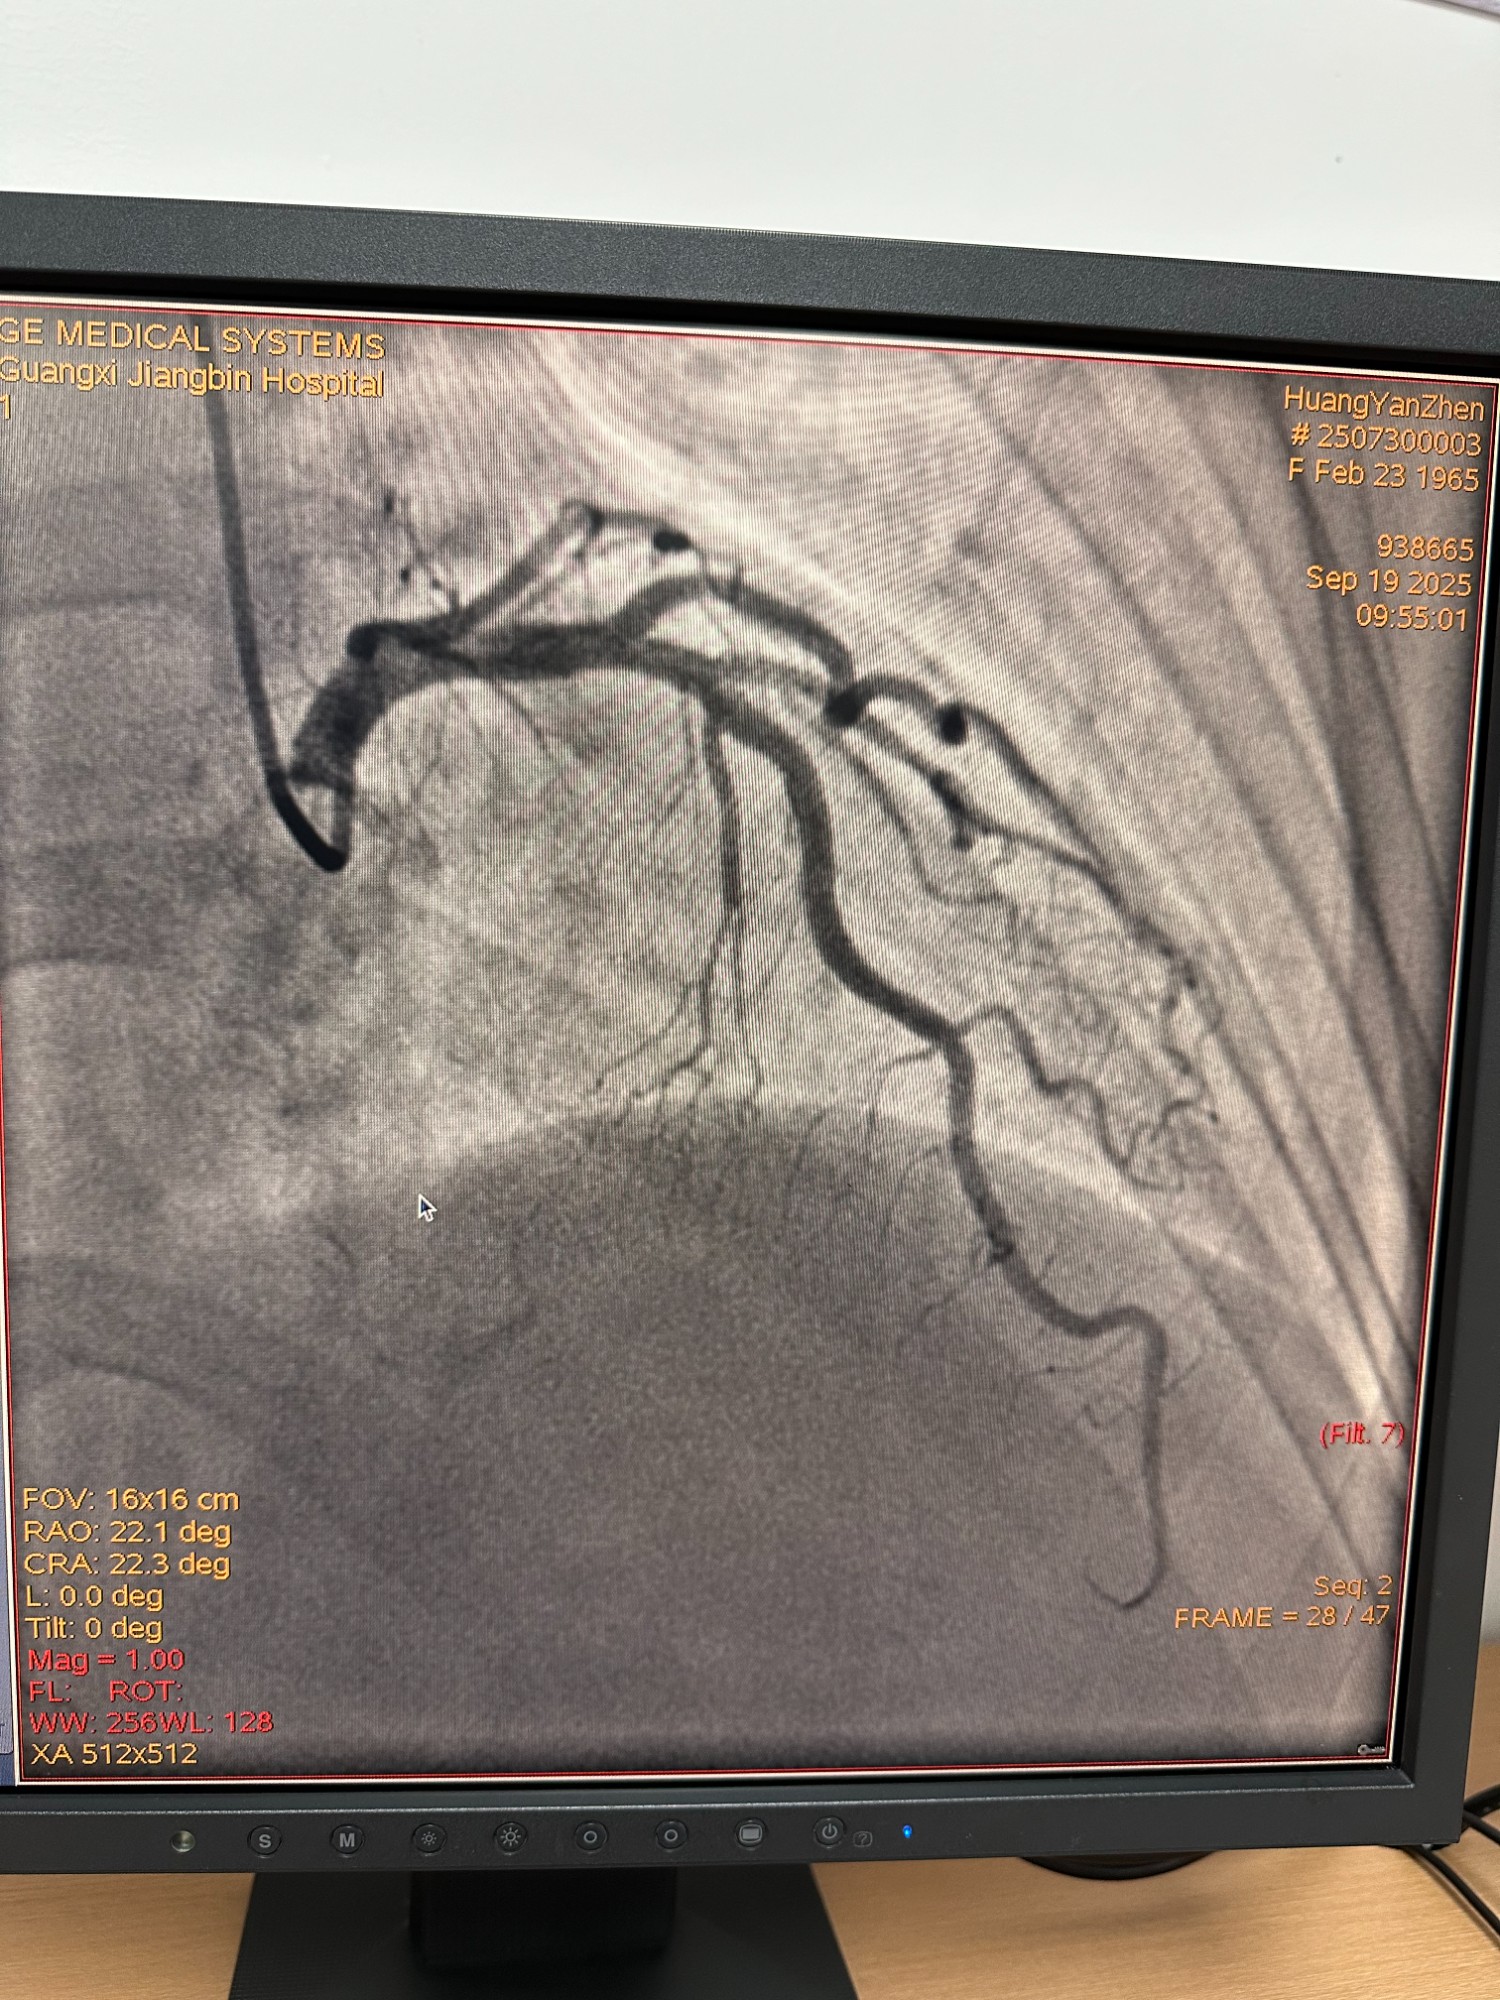

擅长诊治高血压、心绞痛、急性心肌梗死、心力衰竭、各种心律失常、心肌病、心肌炎、心包疾病等心血管常见病和多发病;熟练开展心血管疾病介入性诊疗技术,如冠状动脉造影术,冠状动脉和外周血管支架术,起搏器安置术,结构性心脏病介入术和射频消融术等。老年患者静脉血栓形成的药物和机械预防和治疗,介入性诊断和治疗,如下腔静脉滤器置入术,静脉腔内治疗等。

冠状动脉造影术